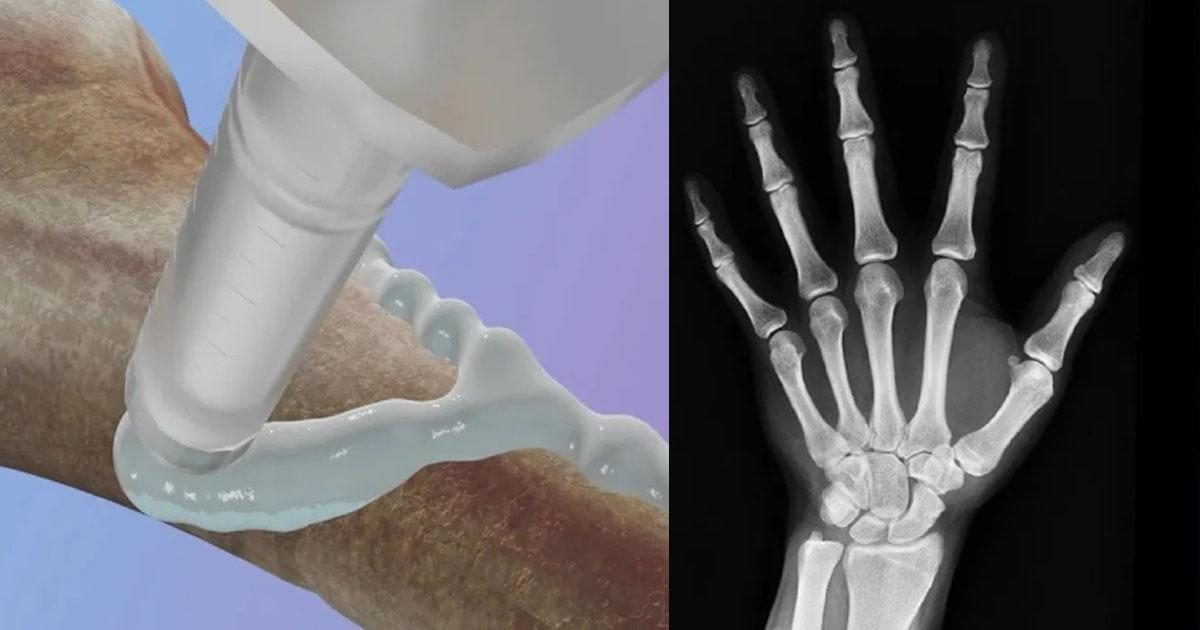

നമ്മുടെ ശരീരത്തിൽ എവിടെയെങ്കിലും എല്ല് പൊട്ടിയാൽ അത് ചികിത്സിച്ച് ഭേദമാകാൻ ദിവസങ്ങളോ ആഴ്ചകളോ എടുക്കാറുണ്ട്. ചിലപ്പോൾ മാസങ്ങളും എടുക്കാറുണ്ട്. ഈ സമയങ്ങളിൽ നമ്മുടെ ദൈനംദിന കാര്യങ്ങൾ പോലും ചെയ്യാൻ വളരെയധികം ബുദ്ധിമുട്ട് അനുഭവിക്കേണ്ടി വരാറുണ്ട്. എന്നാൽ ഇനി അതിന്റെ ആവശ്യമൊന്നും വരില്ല. കാരണം, എല്ലുകളിലെ പൊട്ടൽ ഒട്ടിച്ചുചേർക്കാൻ കഴിയുന്ന വിപ്ലവകരമായ ഒരു മെഡിക്കൽ ബോൺ ഗ്ലൂ അഥവാ പശ വികസിപ്പിച്ചെടുത്തിരിക്കുകയാണ് ചൈനീസ് ഗവേഷകർ.

വെറും മൂന്ന് മിനിറ്റിനുള്ളിൽ പൊട്ടൽ ഒട്ടിച്ചുചേർക്കാൻ കഴിയുന്ന ഗ്ലൂ കിഴക്കൻ ചൈനയിലെ ഷെജിയാങ് പ്രവിശ്യയിലെ ഒരു ഗവേഷക സംഘമാണ് വികസിപ്പിച്ചെടുത്തത്. ഇത്തരത്തിലുള്ള ഒരു ബോൺ ഗ്ലൂ വികസിപ്പിക്കാൻ ഗവേഷകർ വളരെക്കാലമായി ശ്രമം നടത്തുന്നുണ്ടായിരുന്നു. ‘ബോൺ 02’ എന്നാണ് ഈ ഗ്ലൂവിന് പേര് നൽകിയിരിക്കുന്നത്.

ഒരു പാലത്തിന്റെ വെള്ളത്തിനടിയിലുള്ള ഭാഗത്ത് മുത്തുച്ചിപ്പികൾ ശക്തമായി ഒട്ടിപ്പിടിച്ചിരിക്കുന്നത് നിരീക്ഷിച്ചതിൽ നിന്നാണ് ഉൽപ്പന്നം വികസിപ്പിക്കാനുള്ള പ്രചോദനം ലഭിച്ചതെന്നാണ് ഗവേഷകരുടെ ഹെഡും സർ റൺ റൺ ഷാ ഹോസ്പിറ്റലിലെ അസോസിയേറ്റ് ചീഫ് ഓർത്തോപീഡിക് സർജനുമായ ലിൻ സിയാൻഫെങ് പറയുന്നത്. രക്തം വാർന്ന സാഹചര്യങ്ങളിൽ ആണെങ്കിൽ പോലും രണ്ടോ മൂന്നോ മിനിറ്റിനുള്ളിൽ കൃത്യമായി എല്ലുകളെ ഉറപ്പിക്കാൻ ഈ പശയ്ക്ക് കഴിയും.

എല്ലിന്റെ പൊട്ടൽ ഭേദമാകുന്നതിന് അനുസരിച്ച് ഈ പശ സ്വാഭാവികമായി ശരീരത്തിലേക്ക് ആഗിരണം ചെയ്യപ്പെടുകയാണ് ചെയ്യുക. ഈ ഇംപ്ലാന്റുകൾ നീക്കം ചെയ്യാൻ മറ്റൊരു ശസ്ത്രക്രിയയുടെ ആവശ്യവുമില്ല. മാത്രമല്ല, സുരക്ഷ, ഫലപ്രാപ്തി എന്നിവയുടെ കാര്യത്തിൽ ബോൺ-02 മികച്ച പ്രകടനം കാഴ്ചവെച്ചതായി പരിശോധനകളിലൂടെ സ്ഥിരീകരിച്ച് കഴിഞ്ഞു.

പരീക്ഷണഘട്ടത്തിൽ 180 സെക്കൻഡിൽ താഴെ അതായത് മൂന്ന് മിനിറ്റിനുള്ളിൽ ഈ പ്രക്രിയ പൂർത്തിയായി. പരമ്പരാഗത ചികിത്സാരീതികളിൽ സ്റ്റീൽ പ്ലേറ്റുകളും സ്ക്രൂകളും ഘടിപ്പിക്കുന്നത് വലിയ മുറിവ് അവശേഷിപ്പിക്കാറുണ്ട്. എന്നാൽ അതിന്റെയൊന്നും ആവശ്യം ഇല്ല എന്നാണ് ഗവേഷകർ പറയുന്നത്. ഇതുവരെ 150-ലധികം രോഗികളിൽ ബോൺ ഗ്ലൂ വിജയകരമായി പരീക്ഷിച്ചു കഴിഞ്ഞു. ഈ ഗ്ലൂ ഉപയോഗിച്ച് ഒട്ടിച്ച എല്ലുകൾ ശരീരത്തിൽ ശക്തമായി തന്നെയാണ് നിലനിന്നത്. അതിനാൽ പരമ്പരാഗത ലോഹ ഇംപ്ലാന്റുകൾക്ക് പകരമാകാൻ ഈ ഉബോൺ-02ന് കഴിയുമെന്നാണ് പറയുന്നത്.